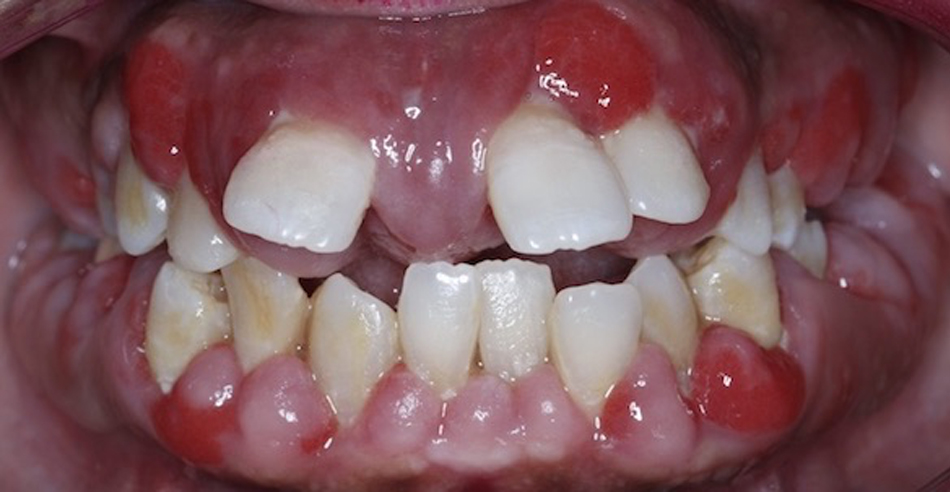

Patient 2 - Before

Pre-treatment patient presentation

Patient 2 - After

Post treatment patient presentation following gum surgery, implant placement and restoration with crowns.